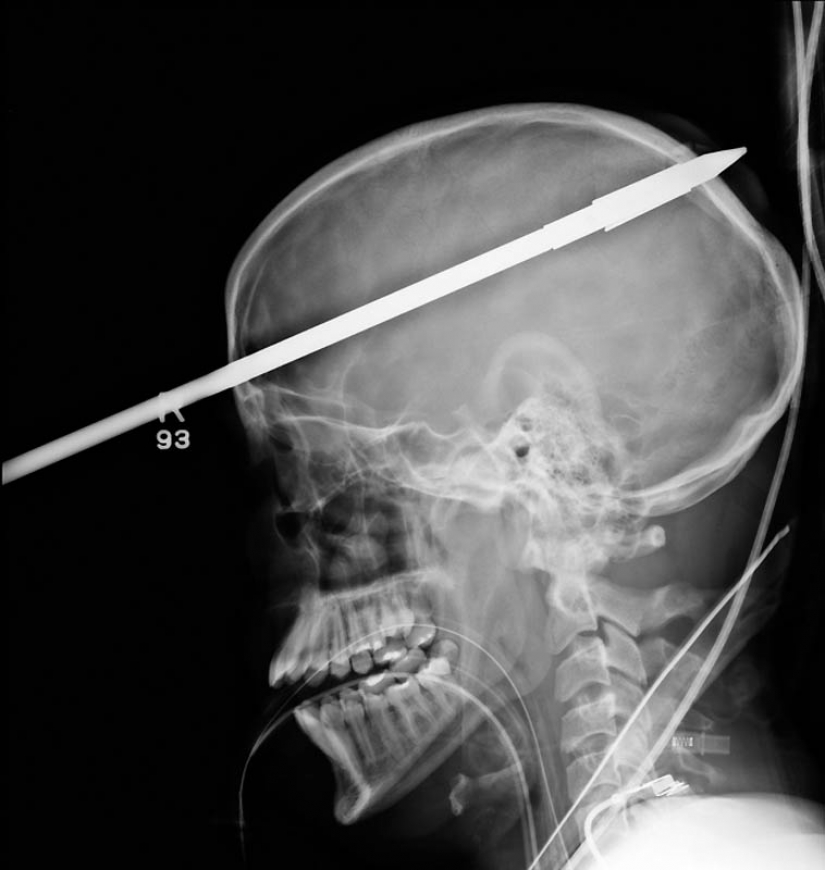

11. La lanza de la arpón, atrapados en la cabeza de un joven de 16 años de edad, niño de pesca.